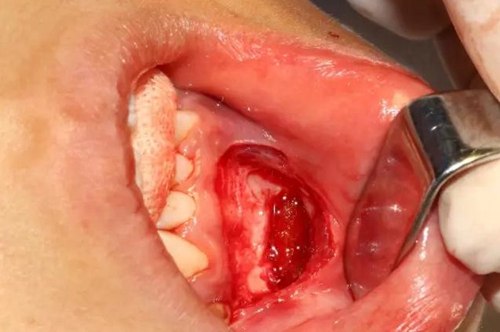

本案:患兒,女,14歲,因牙齒矯正來院,檢查見83滯留,43未見萌出,拍片發(fā)現(xiàn):43埋伏阻生于31、41、42根尖下方,按照正畸診療計劃,擬行43拔除術(shù)。

口腔牙列照片

切開、翻瓣

去除骨皮質(zhì),暴露牙冠大部分